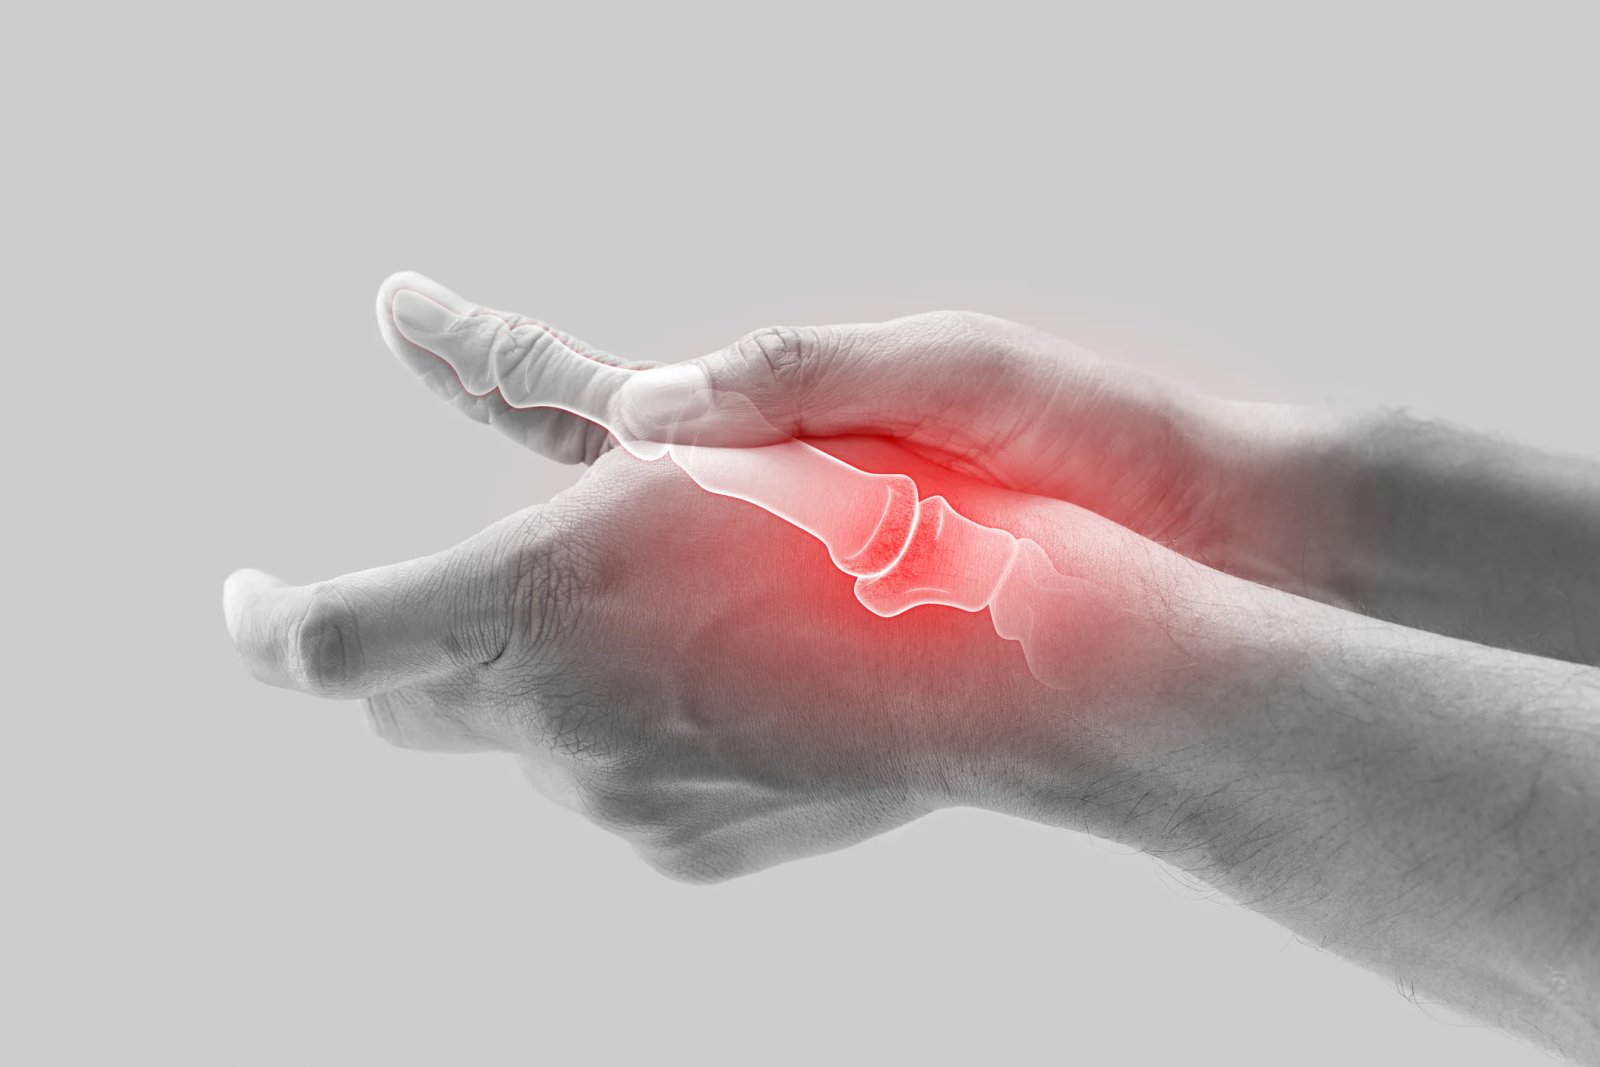

• 1. Arthritis is swelling and pain at one or more joints.

• 2. At SOH we provide comprehensive management of arthritis which includes

• 3. Early diagnosis of different types of arthritis.

• 4. Optimal medical management.

• 5. Prevention of pain and joint deformity and maintaining joint mobility by effective physiotherapy.

• 6. Surgical intervention in end stage disease in form of arthrodesis or joint replacement.